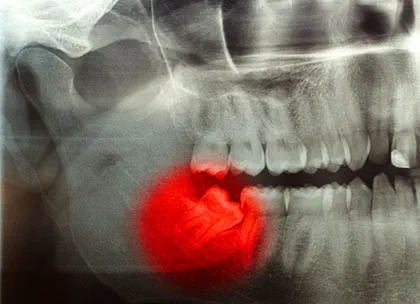

دندان عقل آخرین دندانهایی هستند که در دهان رشد میکنند. آنها معمولاً در اوایل بزرگسالی، بین سنین 17 تا 25 سالگی رشد میکنند. دندانهای عقل در قسمت عقب دهان، در پشت دندانهای آسیاب رشد میکنند. آنها ممکن است در یک ردیف یا در دو ردیف رشد کنند. در برخی از افراد، دندانهای عقل به درستی رشد نمیکنند و ممکن است در دهان گیر کنند یا کج باشند. این میتواند باعث درد، تورم و سایر مشکلات شود.

در برخی موارد، دندانهای عقل روی عصب رشد میکنند. این میتواند باعث درد شدید و سایر مشکلات شود. اگر دندانعقل شما روی عصب رشد میکند، ممکن است لازم باشد آن را بکشید.